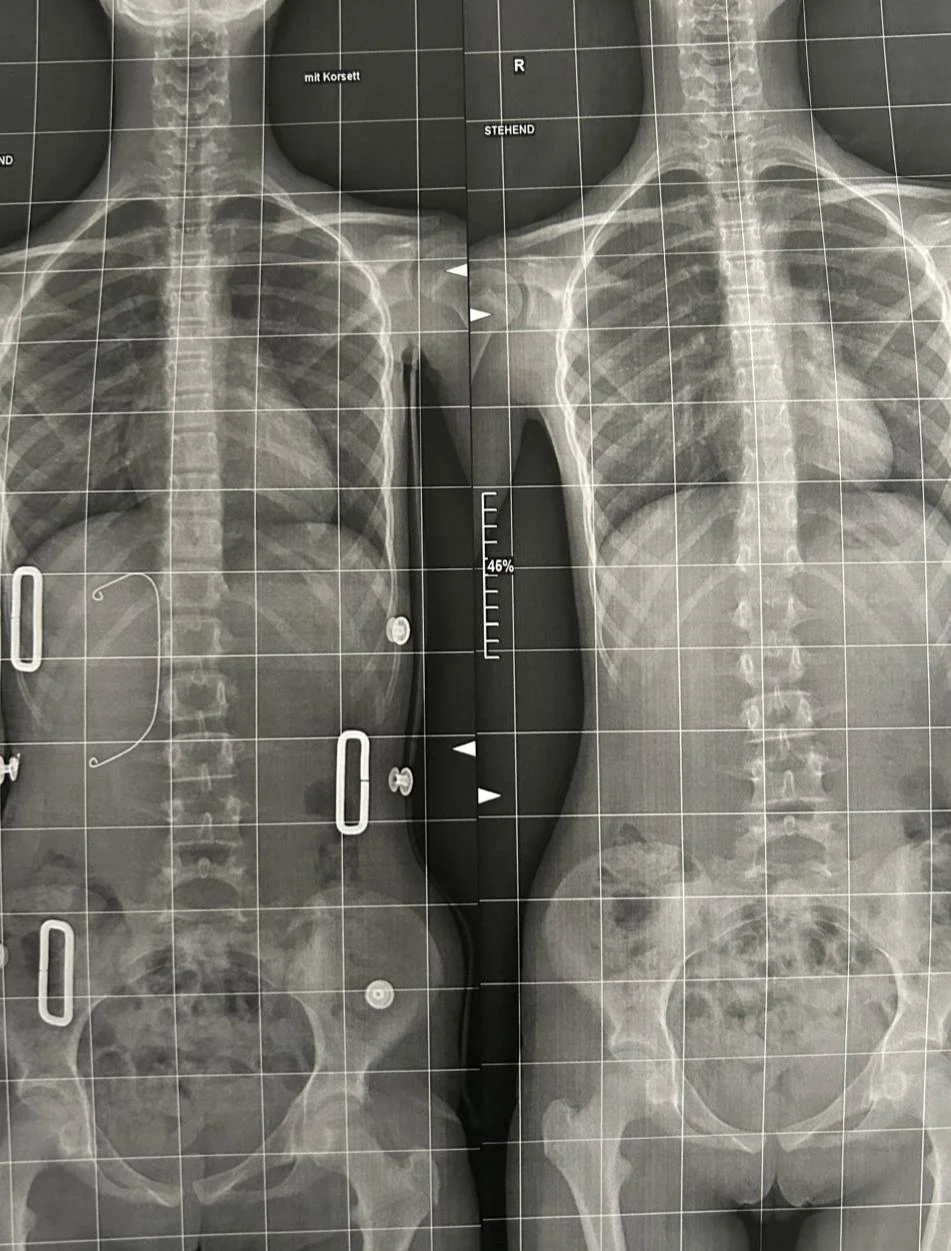

Ausgangssituation und Veränderung nach 3 Behandlungen innerhalb von 5 Wochen. Das zu Beginn der Behandlung angepasste Korsett wurde gleich wieder weggelassen.